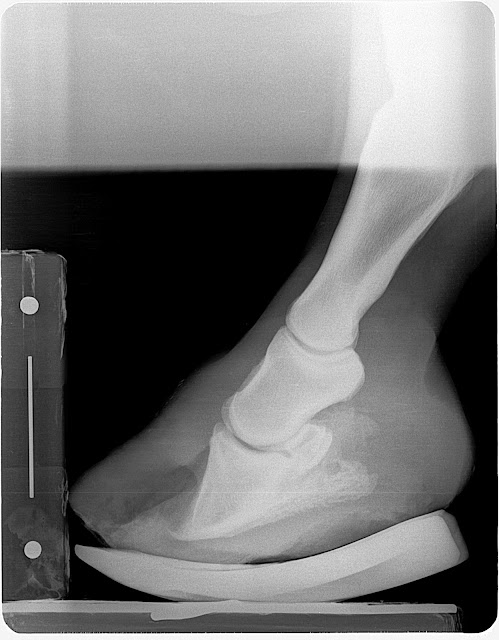

Club foot case: This horse lost the rocker rail shoe applie to the foot opposite the grade 3 club (which is also a club) and regular farrier applied a flat steel keg shoe to keep foot protected. Note the horn lamellar zone divergence. One could call this rotation which would be non specific. The divergence is created by the club syndrome stretching to lower horn to bone attachments. This is confirmed by evaluating the dermal-epidermal junction and measuring the horn zone compared to the lamellar zone. If the lamellar zone was larger than the horn zone one could conclude a laminitis as this is lamellar swelling. In this case it is chronic stretching of the lamellar bone secondary to the constant pull of the deep digital flexor unit.

The Grade 3 club grew more sole in the rocker rail than did the lower grade club in a flat shoe. This information tells us that placing the tendon sling in freedom with the rocker shoe allows better nutrient and blood circulation through unloading of the sole via reduced deep flexor tension. We placed the grade 2 club (Left Front) in a rockered trim with rockered steel keg shoe to also place the tendon sling in release. We will be to see a more rapid sole mass recovery in this hoof as well at the next reset. Owner reports excellent comfort and has adjusted very well to the new shoeing approach.

| Pre shoe radiograph Oct 5 |